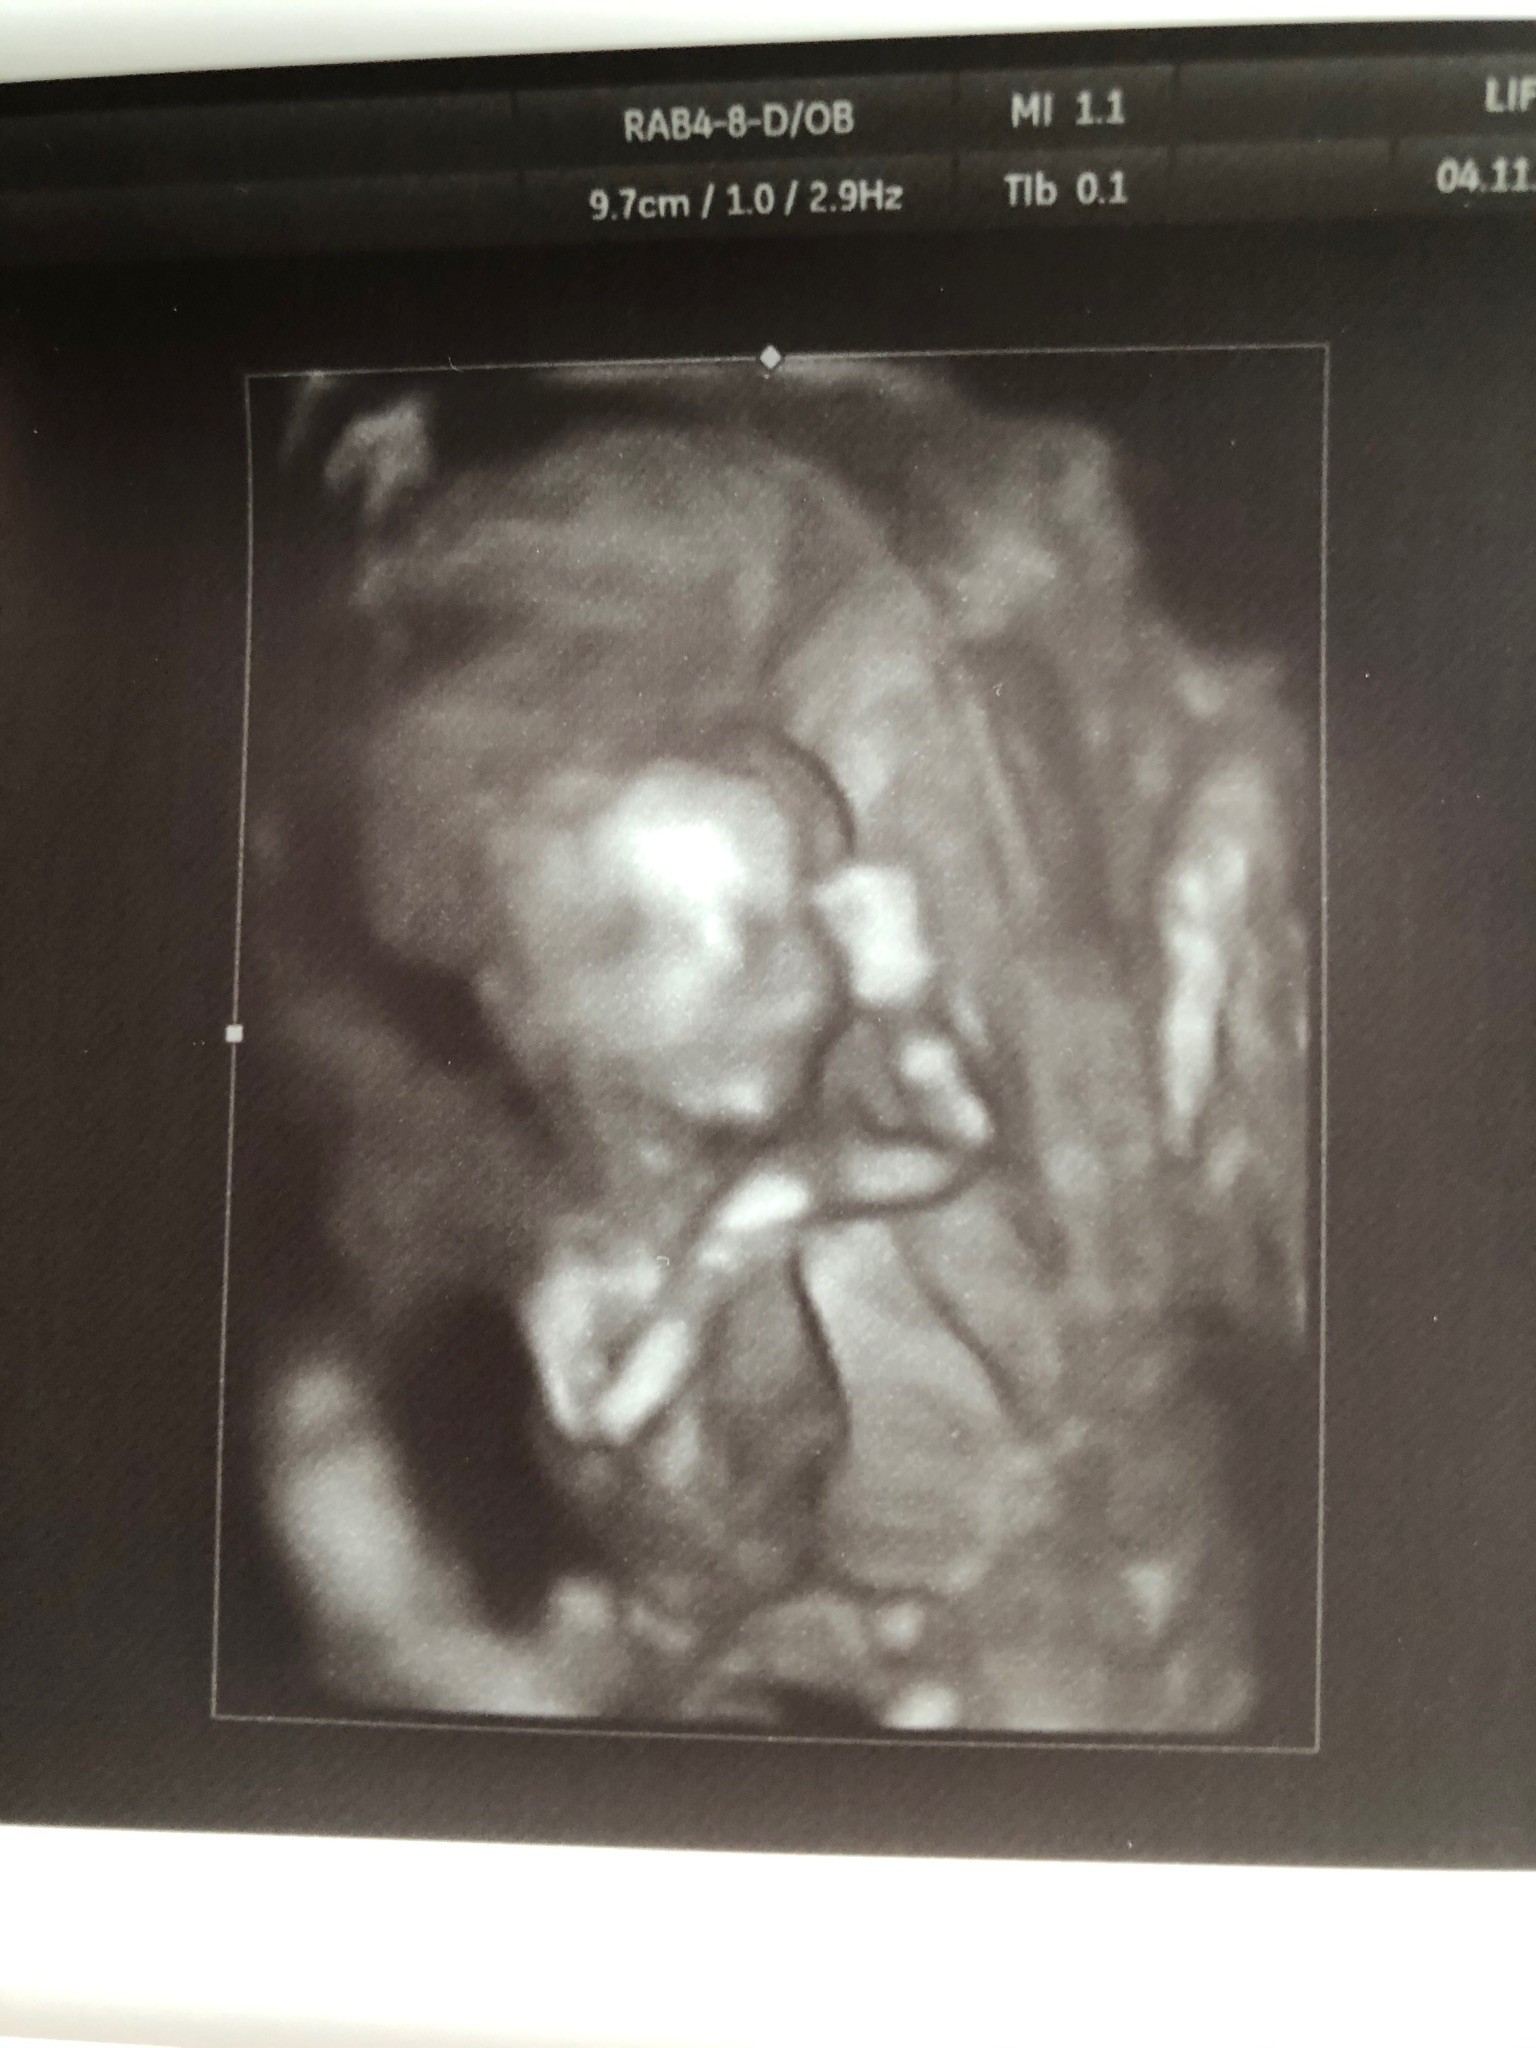

USG za 3 godz. Już nie mogę wysiedzieć w domu, nosi mnie.

My już po wizycie! Oszalałam dziś ze szczęścia - nasze 8 cm okazało się być dziewczynka :rolleyes:

Zobacz załącznik 1041253

I od razu musieliśmy to przypieczętować :yes:

Zobacz załącznik 1041254